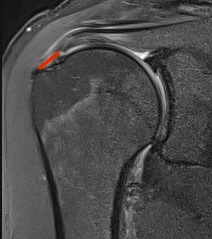

Bursal Sided